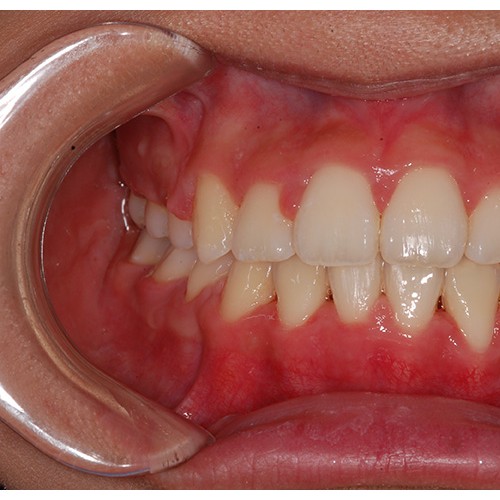

CHUNCHU'S ORTHODONTIC CLINIC# BEFORE_AFTER

춘추치과교정과를 방문해주신 분들의전후 사진을 확인해보세요.